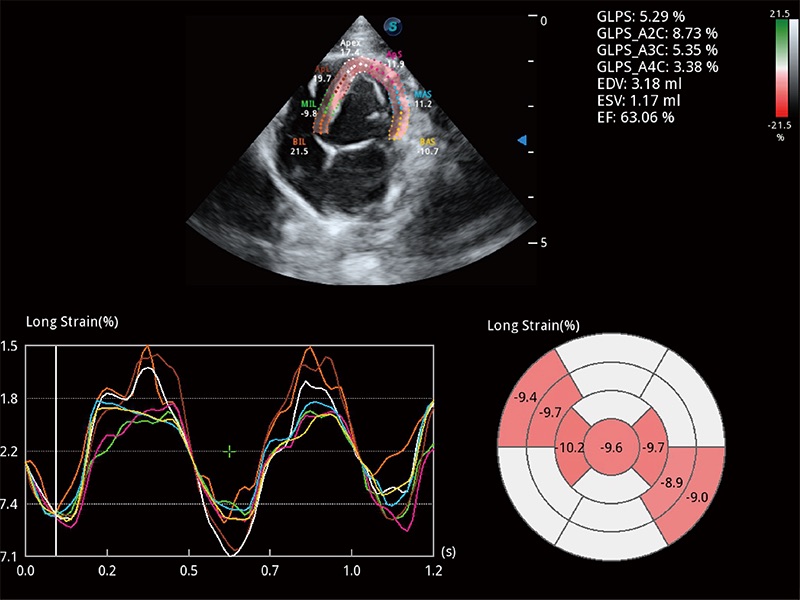

通過心肌識(shí)別技術(shù)與二維斑點(diǎn)追蹤技術(shù)相結(jié)合,對(duì)心臟的超聲圖像進(jìn)行量化分析。計(jì)算心肌17個(gè)節(jié)段的應(yīng)變、應(yīng)變率、速度、位移等,并通過牛眼圖的形式進(jìn)行呈現(xiàn)。

能夠基于左心室壁追蹤和辛普森法,自動(dòng)計(jì)算射血分?jǐn)?shù),支持多個(gè)可移動(dòng)點(diǎn)描跡,與手動(dòng)測(cè)量相比,極大節(jié)省了動(dòng)物醫(yī)生的時(shí)間和精力。